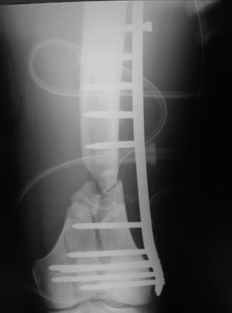

What would be your method of choice to fix this Gr IIIa open high energy supracondylar femur fx, neuro vasculary intact. 30YO male MBA hemodynamically stable, no chest injuries. Right temporal bone fx, no IC bleeding on the head CT. Images attached.

![]() |

Date: 10/31/2004, 12:13 From Zsolt Balogh @ http://weborto.net/ Dear Alex, This is what we have done... As generally true for LISS look at the bone

not the hardware. There are two more screws above. The one not completely

in got damaged head. Zsolt